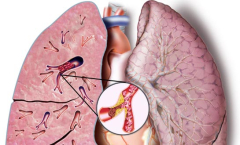

L'embolie pulmonaire est une cause fréquente d'hospitalisation en urgence et de décès. Provoquée par la migration et l'immobilisation d'un caillot de sang dans l'une des artères pulmonaires,...